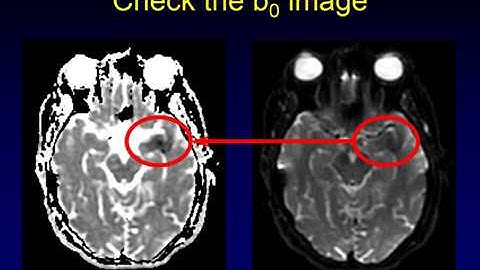

DWI OR ADC IMAGE DIFFERENCE #Dwi or Adc image Identification #Mri Brain Dwi sequence #brain stroke